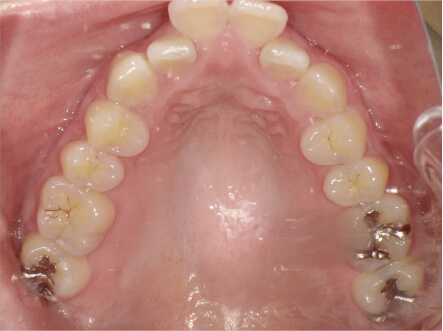

叢生の症例

17歳

/

女性

相談内容

カウンセリング・診断結果

治療内容・方法

全額アライナー矯正

術後の経過・現在の様子

クリアライナー使用

治療のリスク

痛み・歯根吸収・歯肉退縮・虫歯・後戻り

費用・治療期間

715,000円、2年10ヶ月

トレーニングなど